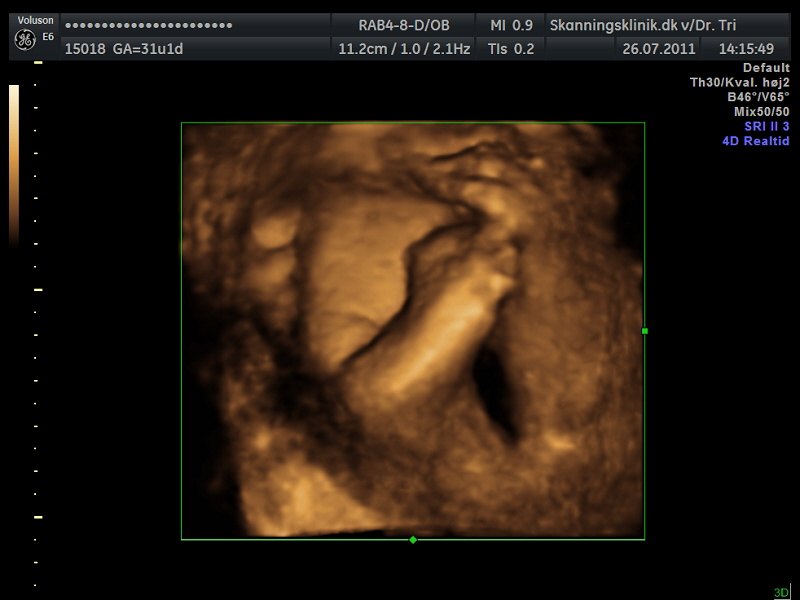

Så blev det tid til en lille 3D/4D-scanning af bettemanden!!

Jeg er i dag 31+2 og var i eftermiddags til 3D/4D-scanning, på skanningsklinikken i Hvidovre, og sikke en oplevelse, helt sikkert alle pengene værd!!

Lillemanden var dog noget svær at få gode billeder af, da han havde skruet numsen ned i mit bækken og synes han skulle ligge med begge hænder og fødder direkte foran hans lille nuttede ansigt hehe.. Så mor her måtte op at hoppe flere gange og fik koldt vand og måtte have maven gennem-rystet flere gange, men alligevel var han nooget på tværs hehe.. Den lille bølle..

Men der kom dog til sidst nogle helt okay billeder ud af det!!

Og så liige lidt billeder, så I også kan se min fine guldklump...

Som I kan se er der lidt hånd og fod med på alle billederne, og på det sidste billede har bettemanden fat om foden med den ene hånd.. Lille hypermobile skid..